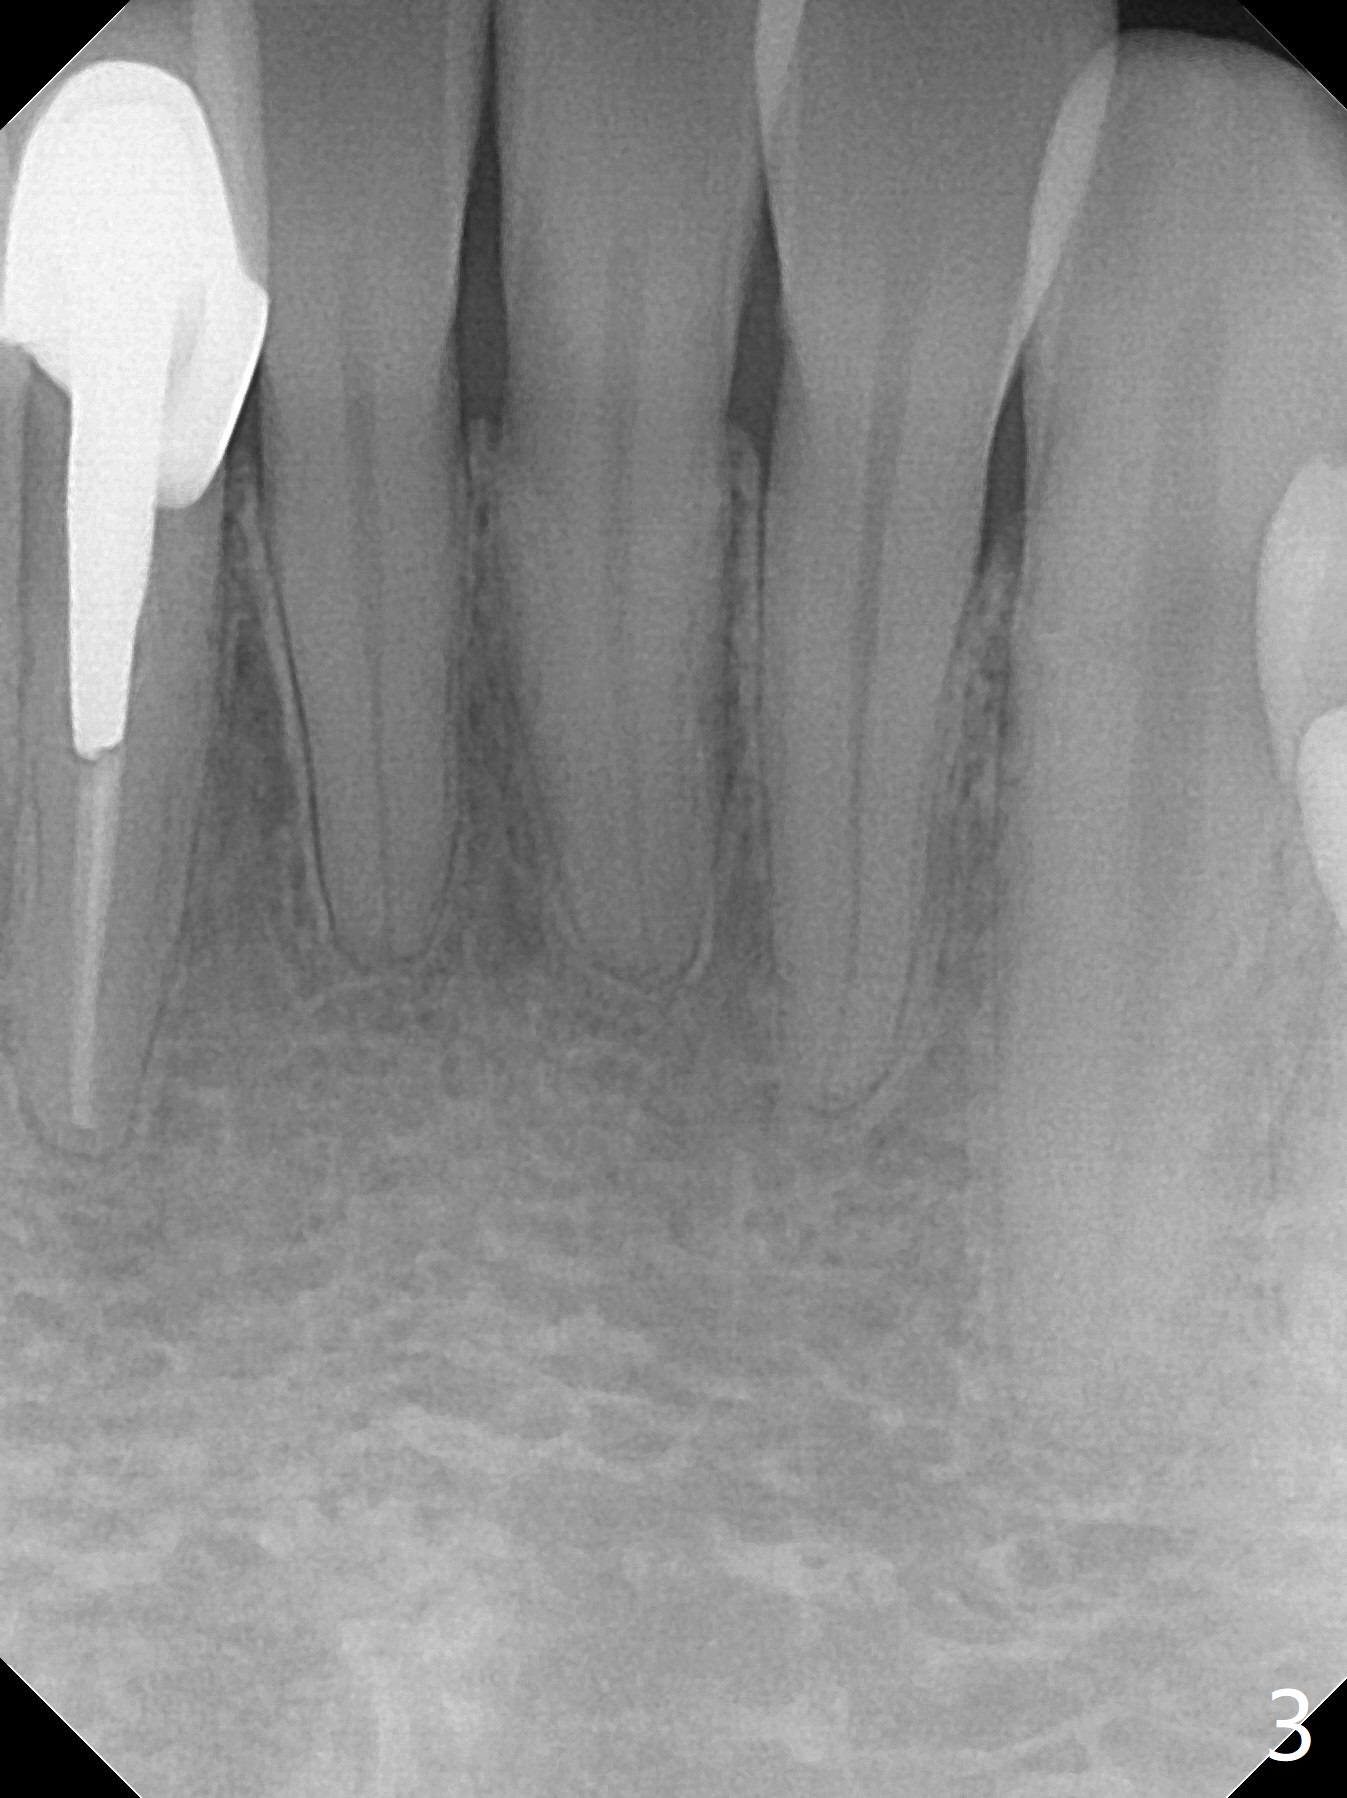

42岁男,小的时候做过矫正,据说智齿萌出后,畸形复发(图一至三)。临床检查显示:上前牙前突,下门牙拥挤,磨牙二类咬合。头颅侧位定位片证明Class II Division I Malocclusion (图四至六):SNA 84.63, SNB 76.11, ANB 8.52。 下周病人复诊,将拍摄照片,取模。正在考虑是否需要拍摄CT,排除上,下切牙是否位于牙槽骨唇侧,有利于做出拔牙决定。